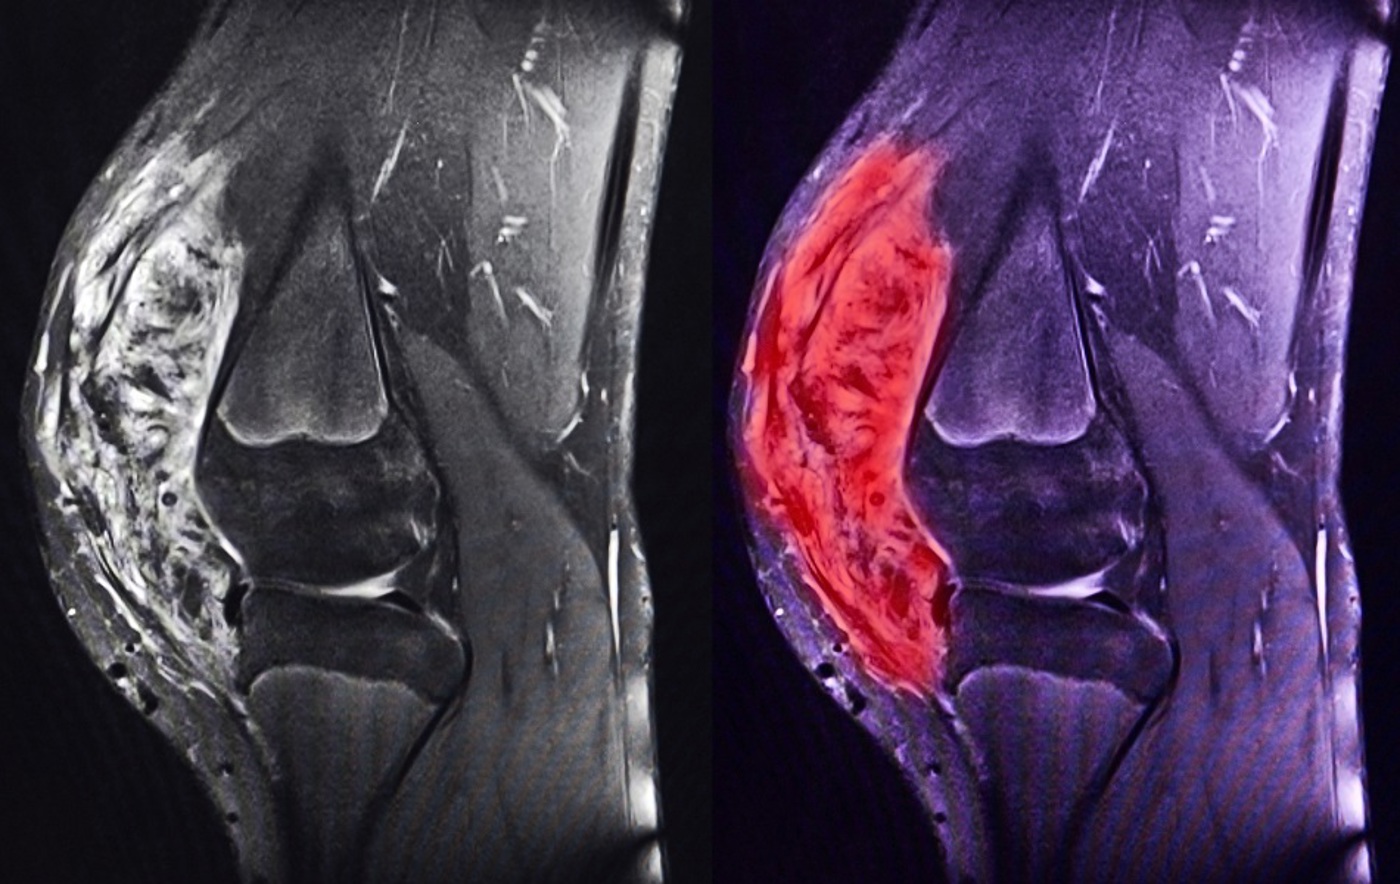

Sarcoma is a rare and complex cancer — and caring for people with sarcoma requires confidence, clarity and a strong grounding in the multidisciplinary pathway.

This on-demand study day provides a flexible, accessible introduction to sarcoma care. Through a series of expert-led recorded sessions, you’ll explore how sarcoma is diagnosed, treated and supported across surgery, systemic therapy, radiotherapy and proton therapy.